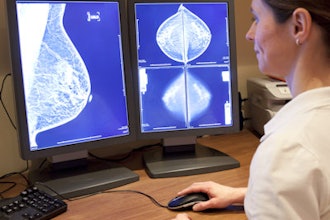

GE HealthCare launches new ABUS system